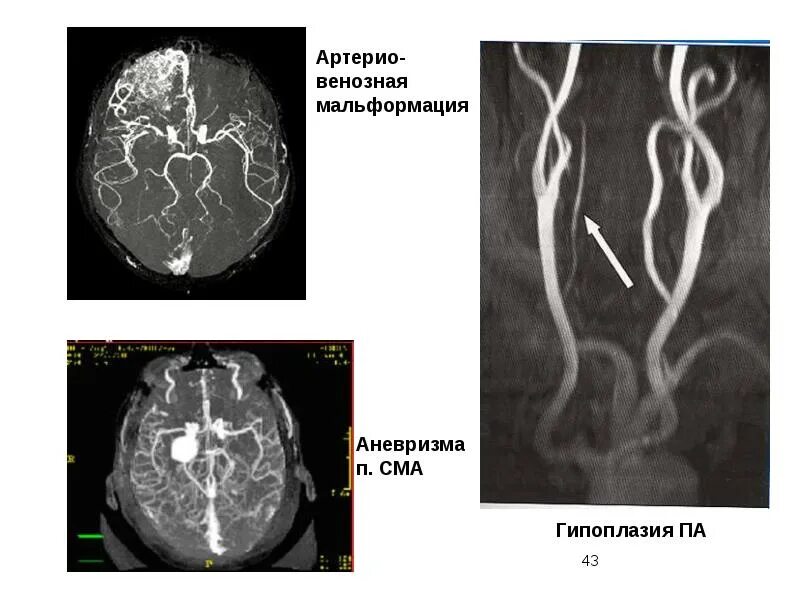

Что такое мальформация головного мозга